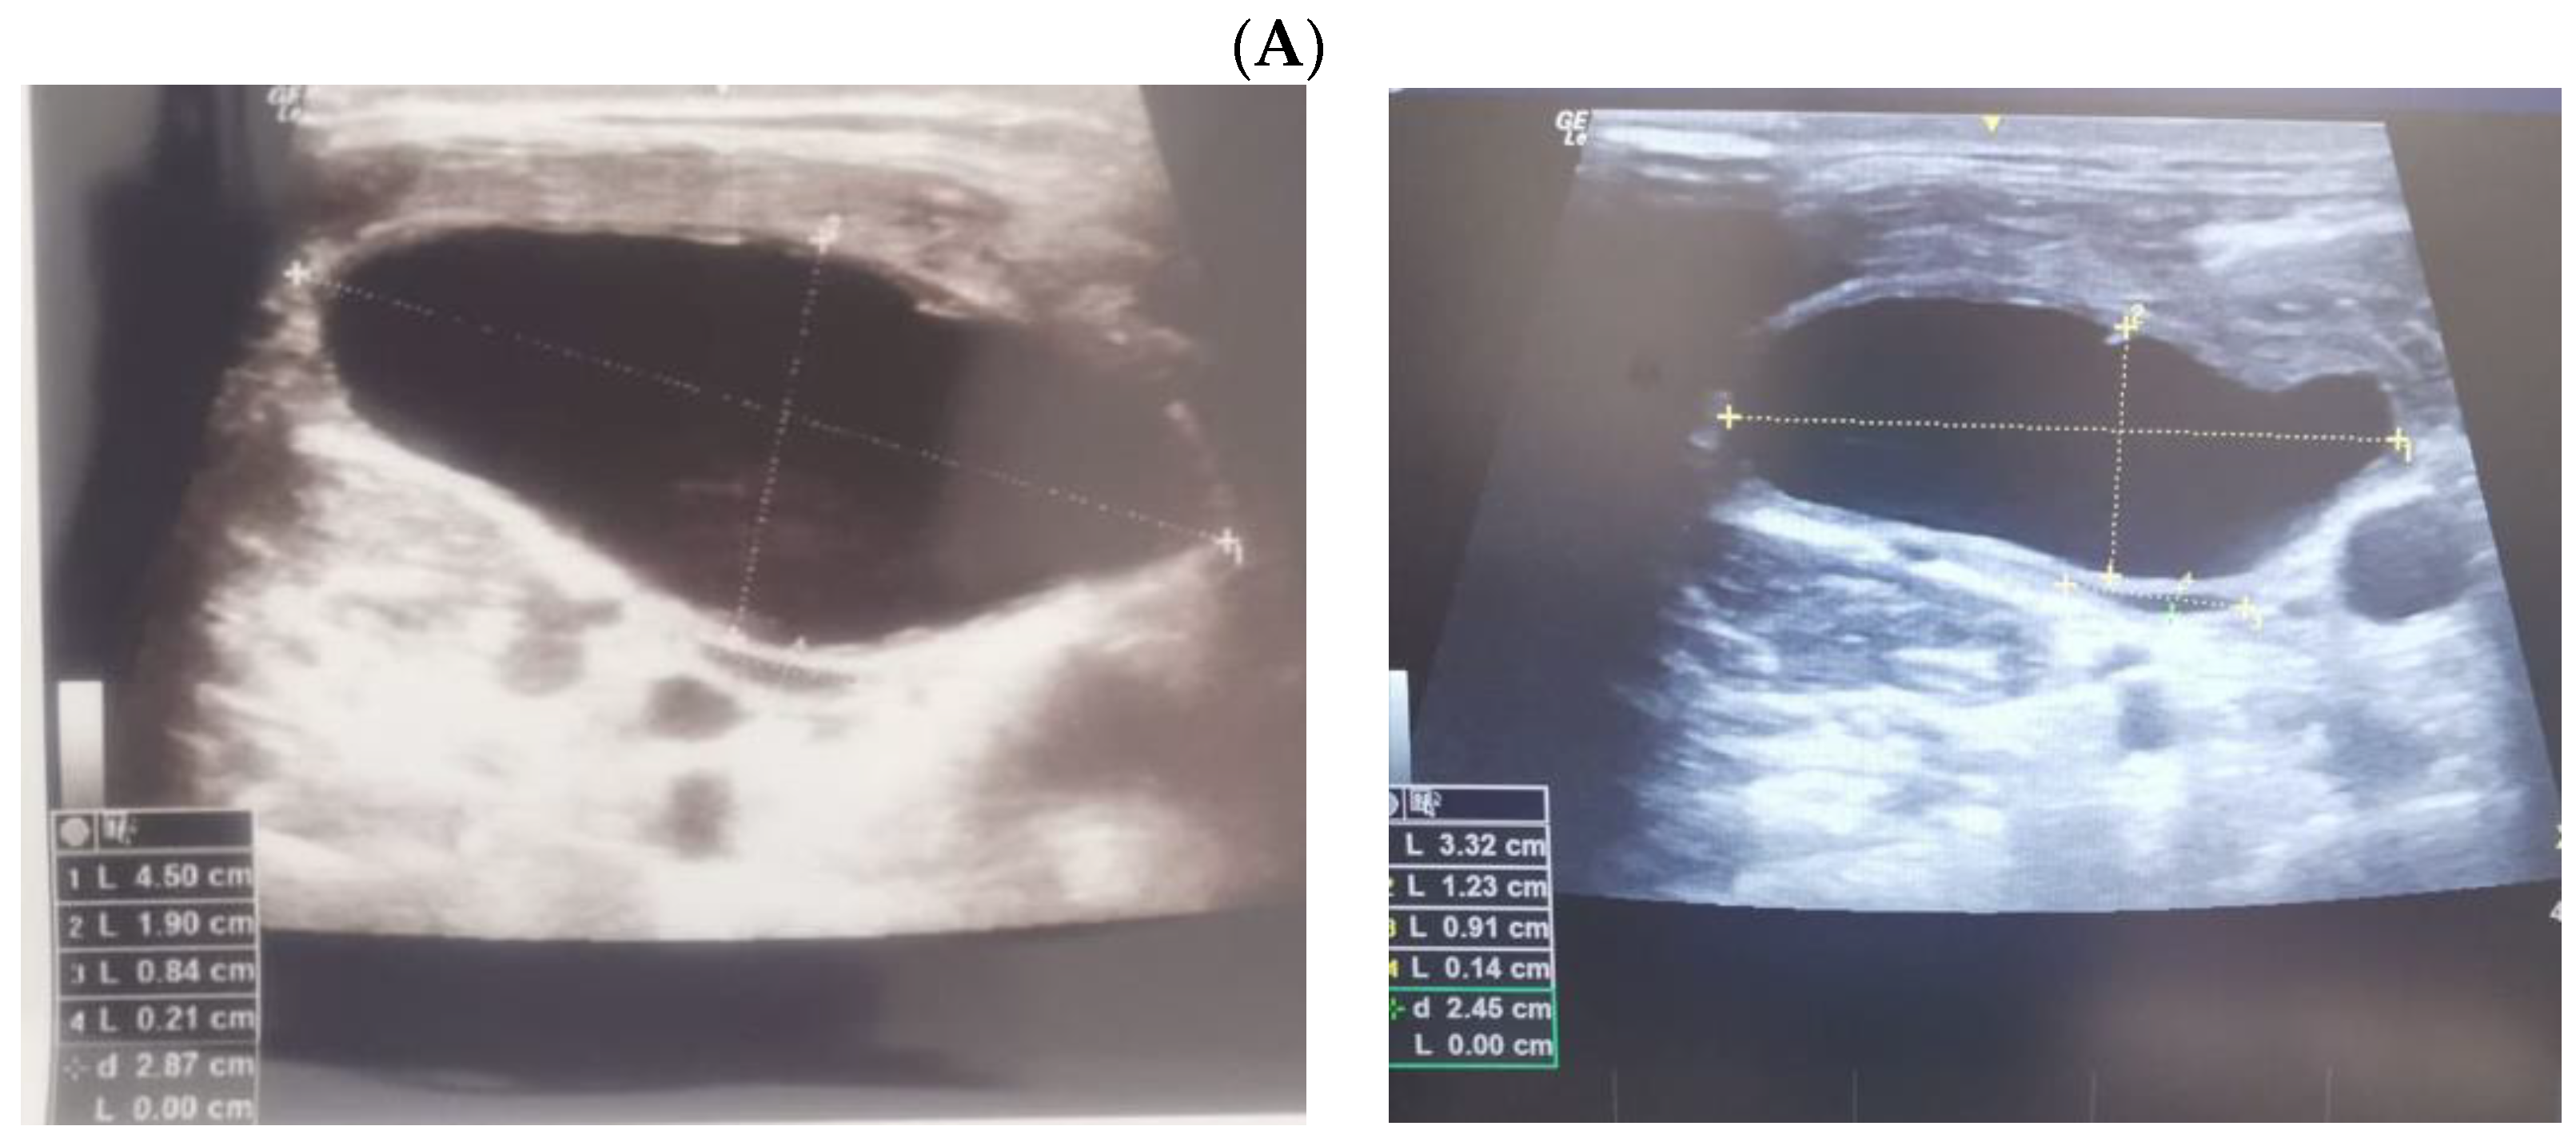

Ultrasound—guided fine need aspiration of the right mass provided cvasi-complete reduction of the liquid with stationary ultrasound features after 90 min. The liquid examination showed mature lymphocytes, rare erythrocytes, rare cholesterol crystals, lymph fluid, consistent with the diagnostic of lymphocele. A mild clinical improvement of HS—associated features was registered, but within 2 days, the neck mass rapidly regrew, and the patient was re-admitted. Under local anesthesia, there was a liquid evacuation (macroscopic aspect with milky-like aspect, a volume of 5–6 mL) and a drain tube was placed for 4 days. Ultrasound aspects showed a progressive regression of the right cystic mass with improvement of HS which slowly remitted within the next 2–3 months. (Figure 4).

Figure 4.

The evolution of within following weeks after thyroid surgery ultrasound features. (A). Right neck ultrasound aspect at the moment of fine needle aspiration (5 weeks since surgery)—on the right and 6 days after fine needle aspiration procedure (after cvasi-complete evacuation, the cystic mass relapsed within 48 h)—on the left. (B). Right neck ultrasound within the first day of tube drainage (6 weeks since initial surgery) showing a massive reduction of the cystic mass. (C). Drainage tube was removed after 4 days. Post-thyroidectomy scar and post-tube removal aspect. (D). Right neck ultrasound after 2 weeks from removing the drainage—persistent cystic mass, but with progressive improvement of HS (approximately 9 weeks since initial surgery). (E). Right neck ultrasound after another 2 weeks from removing the drainage –progressive reduction of cystic mass, but with remarkable improvement of HS (approximately 11 weeks since initial surgery). (F). Scar aspect 12 weeks since surgery and 5 weeks since lymphocele drainage. (G). Recovery of HS—approximately 8 weeks since drainage. (H1,H2). Bilateral neck ultrasound 20 weeks since thyroid surgery showing regression of the lesions on both sides versus prior examinations. (H1). Right later-cervical cystic collection of 2 by 2.8 by 0.9 cm (2.5 mL) and peripheral areas of fibrotic reorganization. (H2). Left later-cervical hypoechoic, inhomogeneous mass (no vascular signal) showing fibrotic reorganization (0.25 mL).